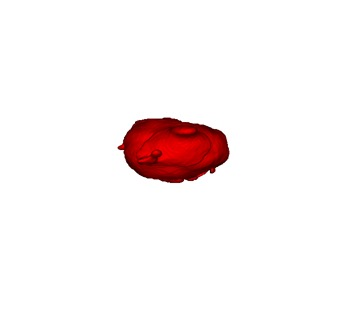

Medical data often exhibits long-tail distributions with heavy class imbalance, which naturally leads to difficulty in classifying the minority classes (i.e., boundary regions or rare objects). Recent work has significantly improved semi-supervised medical image segmentation in long-tailed scenarios by equipping them with unsupervised contrastive criteria. However, it remains unclear how well they will perform in the labeled portion of data where class distribution is also highly imbalanced. In this work, we present ACTION++, an improved contrastive learning framework with adaptive anatomical contrast for semi-supervised medical segmentation. Specifically, we propose an adaptive supervised contrastive loss, where we first compute the optimal locations of class centers uniformly distributed on the embedding space (i.e., off-line), and then perform online contrastive matching training by encouraging different class features to adaptively match these distinct and uniformly distributed class centers. Moreover, we argue that blindly adopting a constant temperature $\tau$ in the contrastive loss on long-tailed medical data is not optimal, and propose to use a dynamic $\tau$ via a simple cosine schedule to yield better separation between majority and minority classes. Empirically, we evaluate ACTION++ on ACDC and LA benchmarks and show that it achieves state-of-the-art across two semi-supervised settings. Theoretically, we analyze the performance of adaptive anatomical contrast and confirm its superiority in label efficiency.

翻译:医学数据经常呈现长尾分布和重度类别不平衡,这自然导致在对少数类别(即边界区域或罕见目标)进行分类时出现困难。最近的研究在长尾情况下通过装备医学影像的无监督对比标准,明显改进了半监督医学图像分割。然而,在标记的数据部分中,类别分布也极为不平衡,因此它们的表现如何仍不清楚。在本研究中,我们介绍一种采用自适应解剖对比度改进的对半监督医学分割行动的框架(ACTION++)。具体来说,我们提出了一种自适应监督对比损失,它首先在嵌入空间上计算出不同类别的优化位置(即离线),然后通过鼓励不同类别之间的特征与这些不同和均匀分布的类别中心相适应的在线对比匹配训练来进行自适应匹配。此外,我们认为,在长尾医疗数据中盲目采用常温度$\tau$不是最优的,因此通过一个简单的余弦计划来使用动态$\tau$来产生更好的多数类别和少数类别之间的分离。在实证方面,我们在ACDC和LA基准测试中评估ACTION++,并展示了其在两种半监督设置下的最新成果。从理论上讲,我们分析了自适应解剖对比度的性能,并证实了它在标签效率上的优越性。